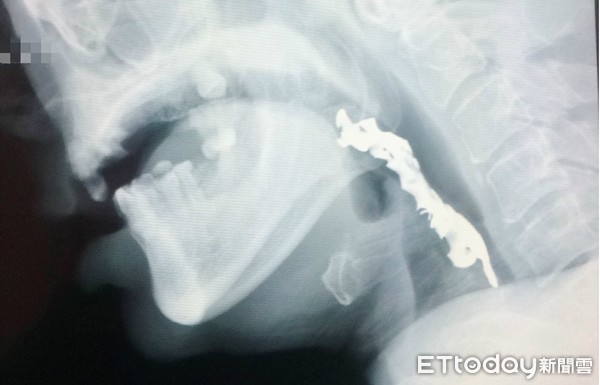

- 常見症狀:假牙卡在喉嚨、食道,可能造成異物感、吞嚥困難、疼痛,甚至阻塞呼吸道。

- 立即就醫:需透過X光或內視鏡檢查,由醫師評估異物位置,必要時使用異物鉗、胃鏡或手術取出。